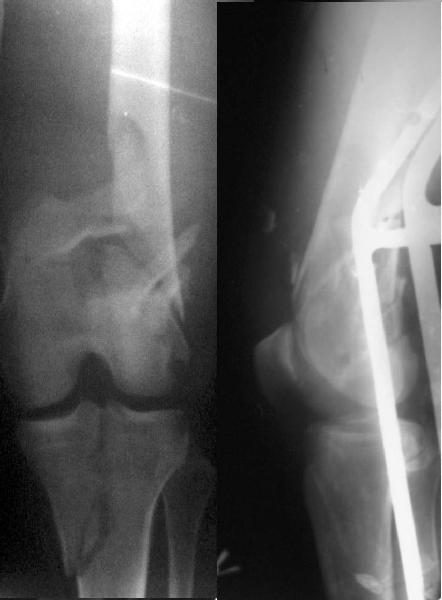

Look what we would have done.